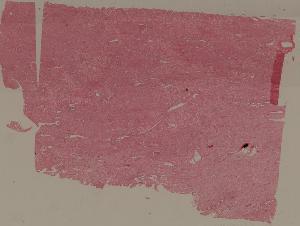

88.慢性纤维空洞性肺结核